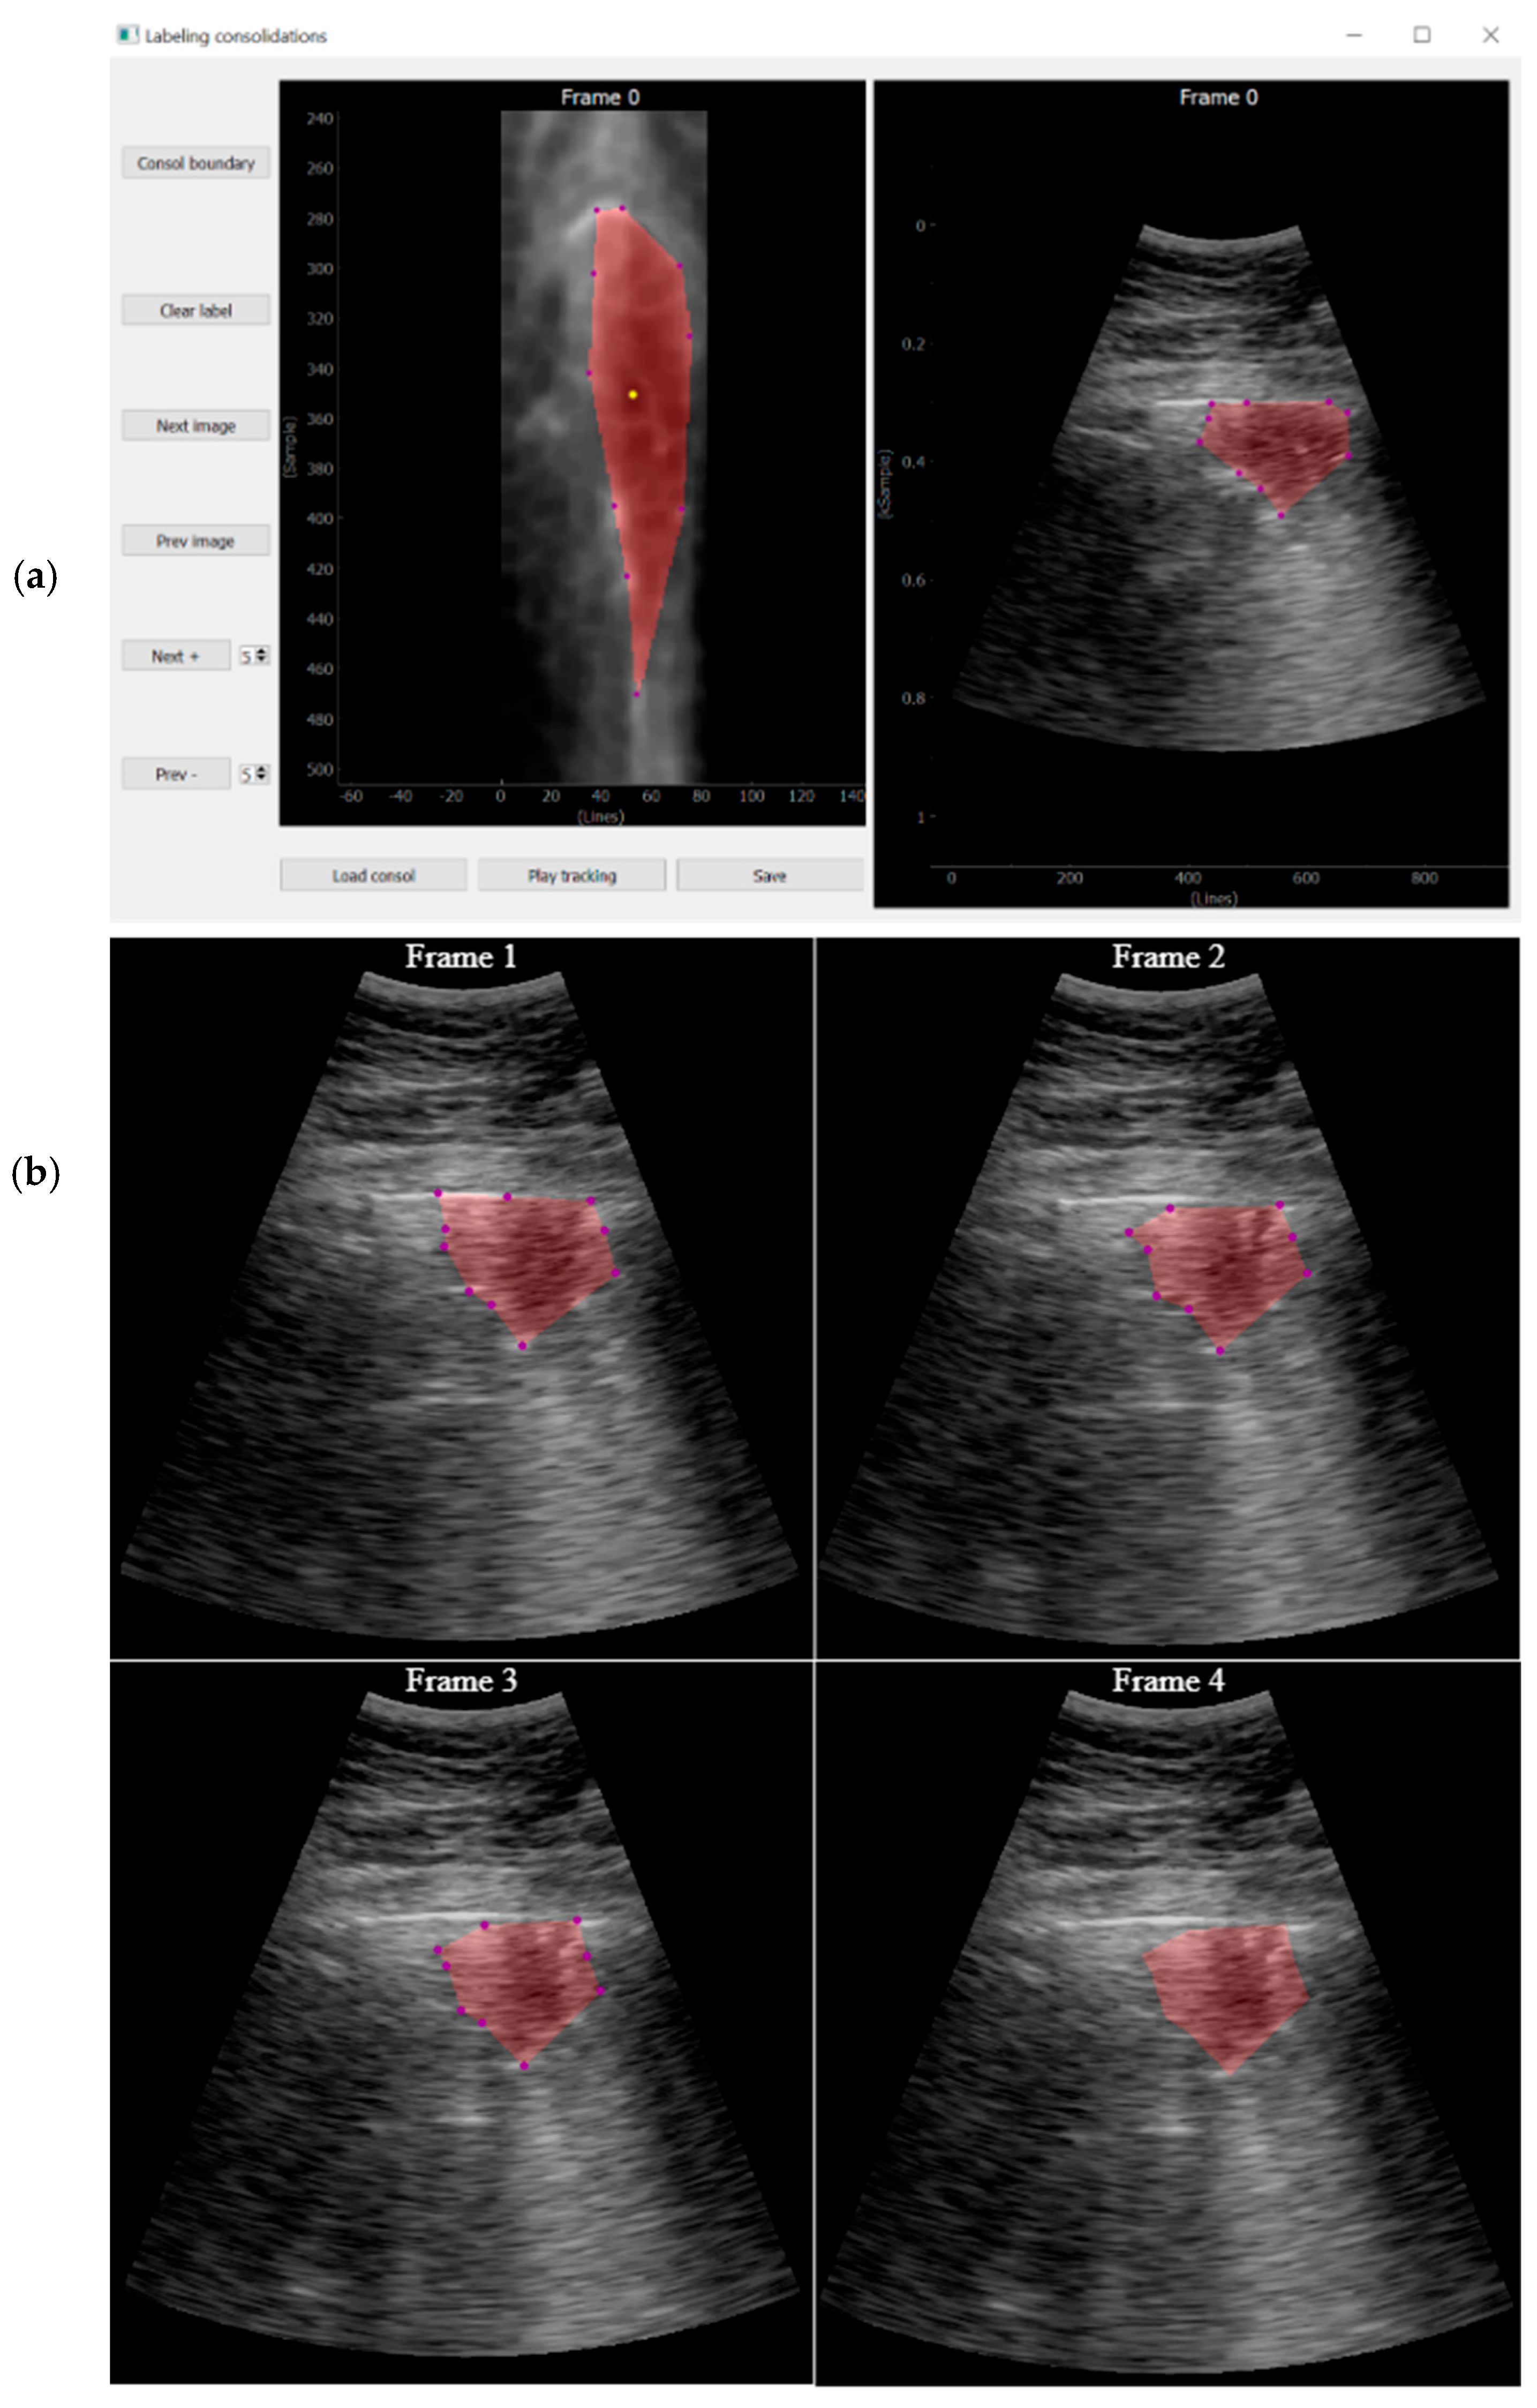

Labelling Tools

CNN Output